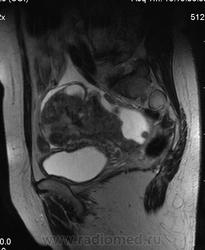

в-целом, cогласен. Карциноматоз тоже есть. Видится еще диффузный аденомиоз матки (задней стенки).

Мне кажется, что есть инфильтрация и передней стенки прямой кишки.